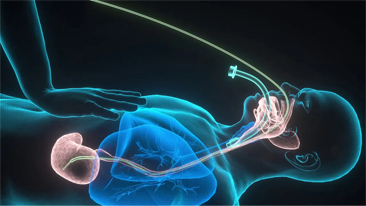

Mindray offers the most comprehensive portfolio of Point of Care ultrasound solutions that are easy to use, elevate your practice, and empower you to provide an even higher standard of care in a timely manner. From entry-level, touch-enabled systems to sophisticated, laptop or cart-based designs, our Point of Care ultrasound machines are an excellent choice to meet the demands of fast-paced environments such as Emergency Medicine, Critical Care, Anesthesia, and others.

MindrayŌĆÖs Point of Care ultrasound machines provide leading-edge technology and everyday applications that meet the diverse demands of your departments and the evolving needs of your patient population. Our innovative, accessible Point of Care ultrasound solutions offer sophisticated tools and technologies that empower you to streamline workflow, minimize the risk of infection, and provide the highest quality of care now and in the future. Experience peace of mind and see something better with Mindray Ultrasound.